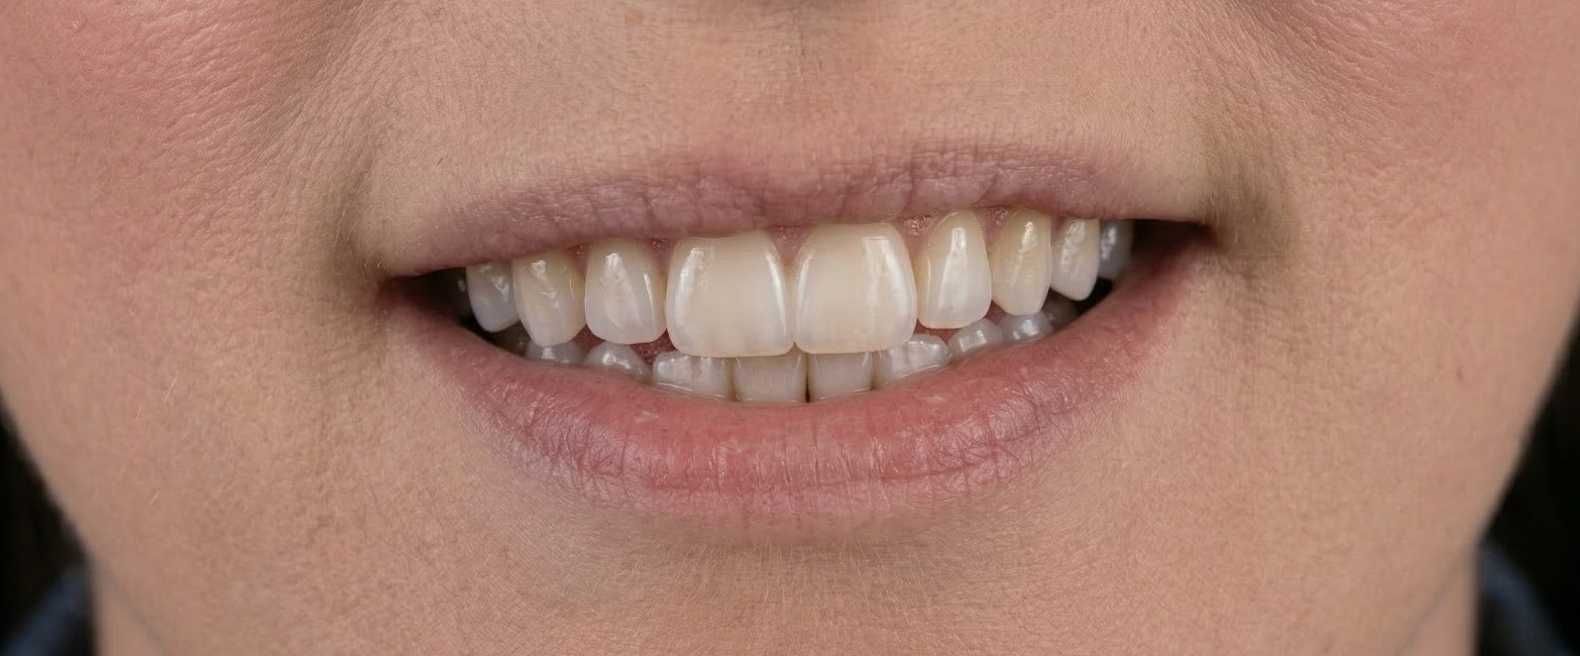

Do gabinetu zgłosiła się pacjentka około 45 roku życia, która oczekiwała efektu lekkiego nawilżenia i wyrównania asymetrii ust.

Źródło: zdjęcie własne. Usta pacjentki przed zabiegiem.

Źródło: zdjęcie własne. Usta pacjentki przed zabiegiem.

Zabieg przebiegł bezproblemowo. Efekt był zgodny z oczekiwaniami. Pani zgłosiła się 3 tygodnie po zabiegu, ponieważ usta po modelowaniu jej się podobały, ale…

Jej uwagę przyciągnął środek dolnej wargi - niewielkie zagłębienie, które zaczęła odbierać jako coś nieprawidłowego.